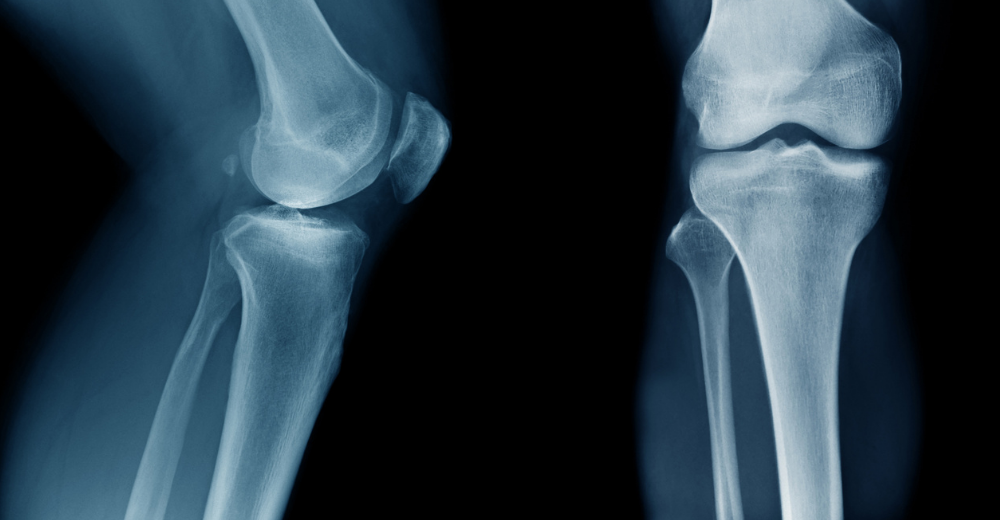

L’esame RX Assiali della Rotula è una procedura radiografica che utilizza i raggi X per generare immagini dettagliate della rotula e delle sue strutture circostanti. All’interno del Poliambulatorio S-Medical Group di Sora, questo esame è condotto con una professionalità e una precisione elevate.

Presso il Poliambulatorio S-Medical Group di Sora, l’esame RX Assiali della Rotula ha un ruolo fondamentale nella diagnosi delle condizioni patologiche che interessano questa articolazione. Le immagini fornite dall’esame consentono ai medici di identificare fratture, usura, anomalie strutturali e altre problematiche che possono compromettere la funzionalità e la salute della rotula.

Grazie all’esame RX Assiali della Rotula eseguito presso il Poliambulatorio S-Medical Group di Sora, gli specialisti ottengono immagini chiare e dettagliate della rotula, delle articolazioni e delle strutture adiacenti. Queste immagini permettono di valutare l’allineamento, la forma e lo stato di salute generale della rotula, individuando segni di patologie o lesioni.